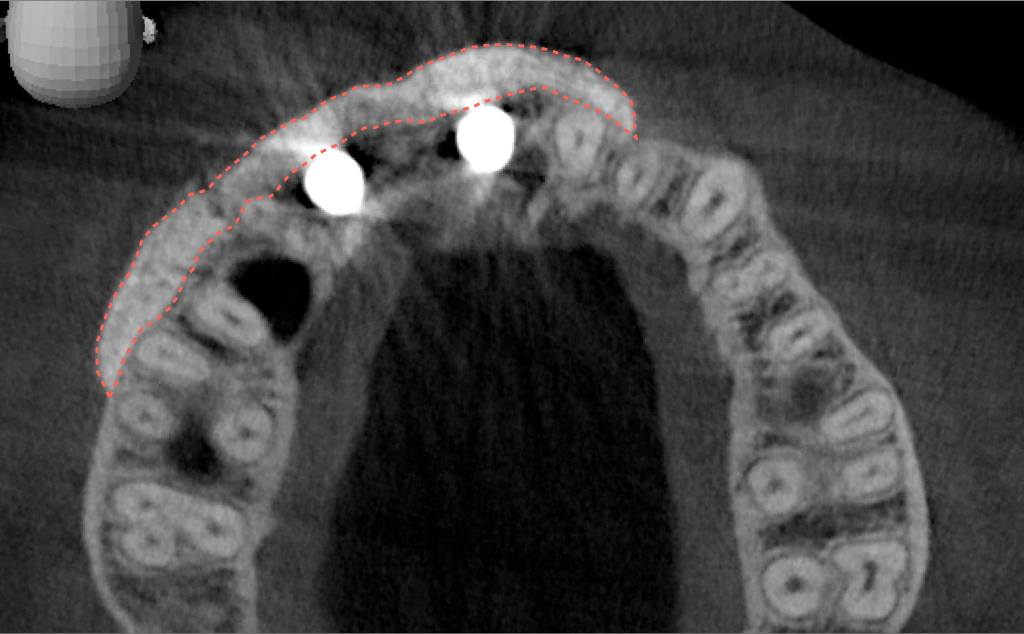

Tomographic images revealed a large tridimensional defect, with vertical and horizontal loss of bone extending to the apical third of teeth Nos. 6 and 8. Additionally, a buccal bone dehiscence was evident on tooth No. 5, and thin labial plates secondary to the orthodontic movement were present in several areas (Figure 3 and Figure 4).